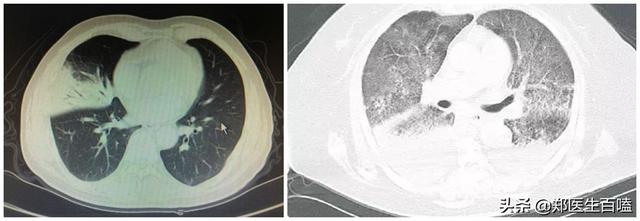

(Pneumonie lobaire typique (infection bactérienne) à gauche, pneumonie virale à droite)